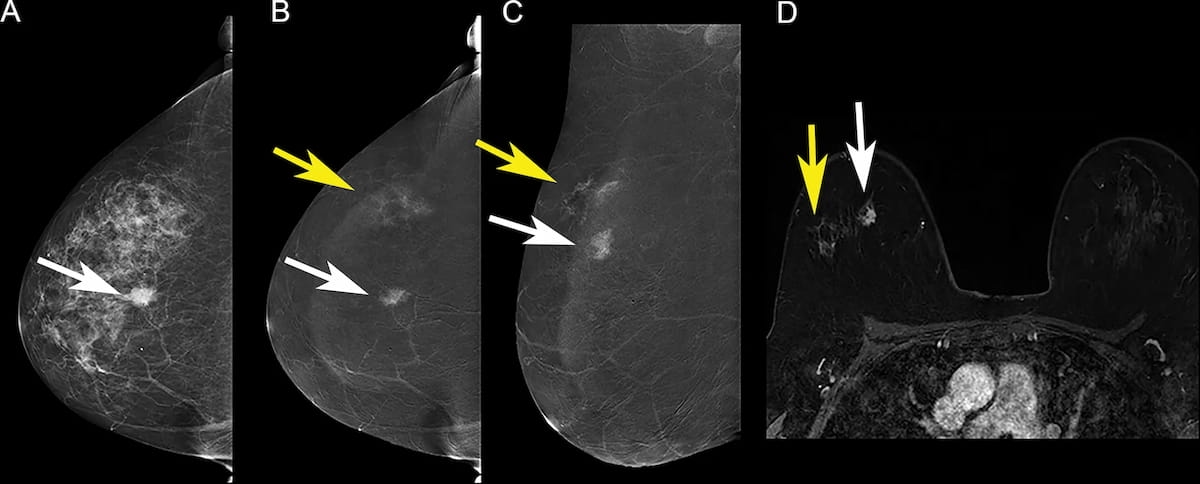

In multiple mammography datasets with the original radiologist-detected abnormality removed, deep learning detection of breast cancer had an average area under the curve (AUC) of 87 percent and an accuracy rate of 83 percent, according to research presented at the recent Society for Imaging Informatics in Medicine (SIIM) conference.